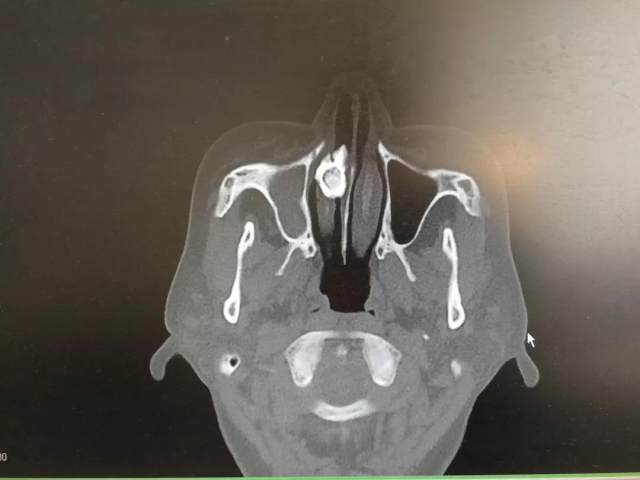

于医生让王女士仔细回忆是否有异物进入鼻腔史,被王女士一口否认。为明确诊断,于甲瑞马上安排患者做了鼻部 CT 检查。结果片子上显示「右侧鼻底类圆形高密度影」,虽然下鼻甲及鼻底明显变形,但骨质无破坏,考虑就是鼻腔异物。